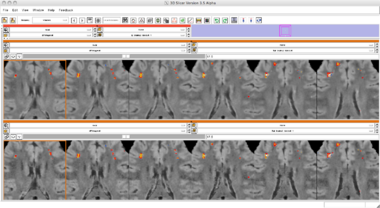

Slicer3 Module Lesion Classification

Lesion Classification Result